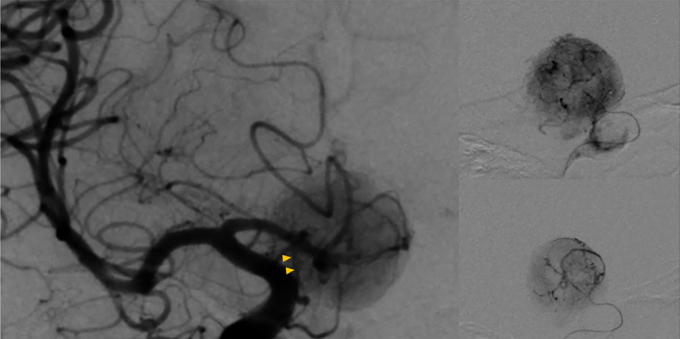

挑战环节二体现在肿瘤血供状态极为丰富、术中出血风险极高的特点方面。针对垂体细胞瘤高度血管化的已知特性,福教授在手术开始之前专门安排了数字减影血管造影检查,精准定位了肿瘤的主要供血动脉——主要来源于左侧的垂体上动脉分支。

福教授作出的决策是:在手术之前进行血管栓塞处理,切断肿瘤的主要血供来源。血管造影结果显示,栓塞后的肿瘤供血动脉重建率达到了百分之九十的水平,栓塞线圈在垂体上动脉内部清晰可见。这一关键步骤为后续的手术操作奠定了安全的血流控制基础——整个手术过程中没有出现任何明显的出血状况及相关并发症的发生。